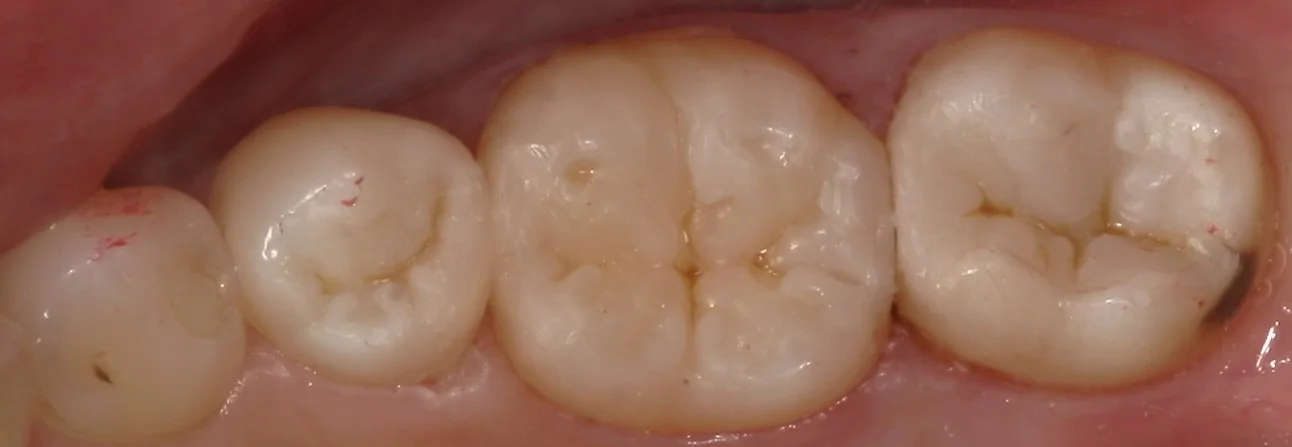

そして、詰め終わたのがこちらの写真です。

長時間の処置だったため、乾燥しており、詰めた部分が浮いているような感じになっていますが、1週間もすると歯に水分が戻り、違和感が無くなってきます。